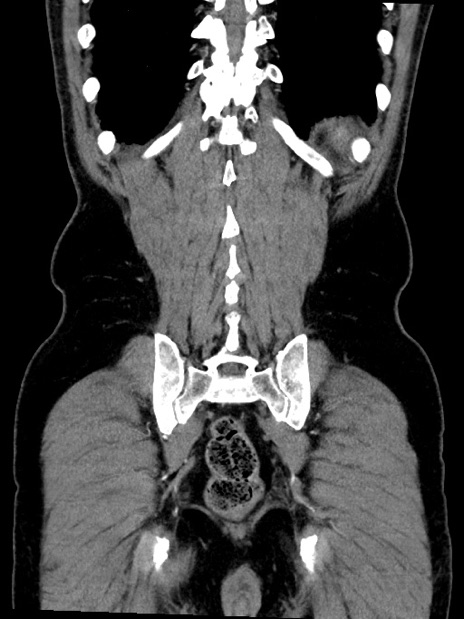

症例35(冠状断像)

【症例】70歳代 男性

【主訴】腹部膨満、嘔吐

【現病歴】昨日より腹部膨満感出現。本日増悪し、仙痛出現。嘔吐あり、受診。

【既往歴】糖尿病、胆摘後

【身体所見】BP 149/80mmHg、HR 74/min、BT 35.9℃、腹部:膨満、軟、圧痛なし。腸雑音減弱あり。上腹部正中切開瘢痕あり。

【データ】WBC 13500、CRP 1.72